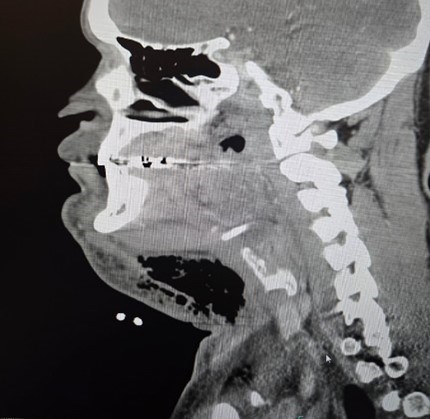

(Left: Figure 1 | Right: Figure 2)

CT soft tissue neck revealed extensive soft tissue swelling with gas formation in the left facial and cervical regions concerning for necrotizing fasciitis, along with narrowing of the hypopharyngeal and laryngeal airway.